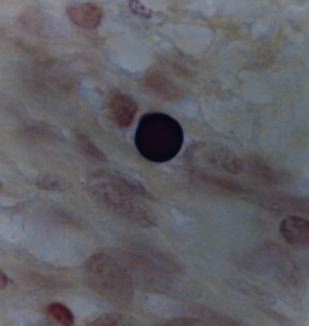

Figure 8. Tissue section from Hodgkin’s lymphoma of a lymph node showing a solitary giant, “large body” or Russell body. Gram stain, x1000, in oil.